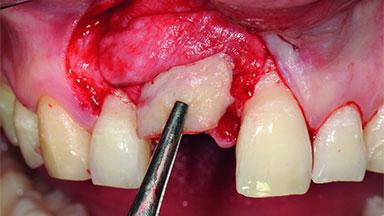

Replacement of a Compromised Upper Right Central Incisor: Hard- and Soft-tissue Augmentation, Late Placement of an RC Bone Level Implant

A 36-year-old male patient with a compromised maxillary central incisor was referred by his general dentist for consultation. The patient’s chief complaints were the gradual debonding of a temporary crown on the right central incisor and unsatisfactory esthetics due to an increasing diastema between the right central and lateral incisors. The patient reported a traumatic event some years previously, when a crown had been placed after root-canal treatment. The referring dentist wanted to provide a new crown restoration, but was concerned about the condition of the residual root. Anamnesis was negative for any other dental or periodontal pathology in the remaining dentition. The patient reported taking no medications: He was a smoker (10 to 15 cigs/day) and had realistic esthetic expectations.

Bone Augmentation Horizontal|Simultaneous|Staged

Augmentation Materials Xenogenous|Membrane

Soft Tissue Grafting Simultaneous

Bone Volume Deficient horizontally, requiring prior grafting